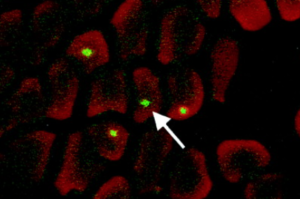

Opracowano kilka metod mikroskopii immunofluorescencyjnej do wykrywania różnych gatunków Bartonella, ale nie są one jeszcze rutynowo stosowane.

Rysunek 5. Obraz z laserowej mikroskopii konfokalnej wewnątrzkomórkowej infekcji Bartonella quintana znakowanej specyficznymi przeciwciałami immunofluorescencyjnymi

Rysunek 6. Obraz mikroskopowy immunofluorescencyjny zakażenia Bartonella henselae znakowany swoistymi przeciwciałami immunofluorescencyjnymi w węźle chłonnym pacjenta z „chorobą kociego pazura”.

Rysunek 7. Obraz mikroskopii immunofluorescencyjnej zakażenia Bartonella henselae znakowany swoistymi przeciwciałami immunofluorescencyjnymi we krwi naturalnie zakażonego kota.